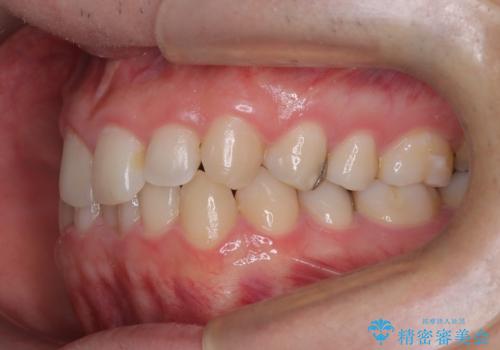

前歯のガタつきと逆の噛み合わせを、短期間のインビザラインで改善

- 前歯の叢生(ガタつき)と、上下の噛み合わせが一部逆になっている反対咬合を主訴にご来院されました。精密検査の結果、前歯の移動だけでは不十分で、歯列全体のアーチを整えながらスペースを確保する必要があると診断。

中等度の症例に最適で最大26ステージ(※プランによる)のマウスピースが使用可能な**「インビザライン・モデレート」**を選択しました。これにより、抜歯をせずに歯列を横に広げ(側方拡大)、前歯を並べる十分なスペースを作りながら反対咬合を確実に改善する計画を立案しました。

反対咬合の解消: 内側に入っていた前歯を、マウスピースの力を利用して外側へ押し出しました。同時に、下顎の歯並びも微調整することで、スムーズに正常な噛み合わせへと誘導しました。